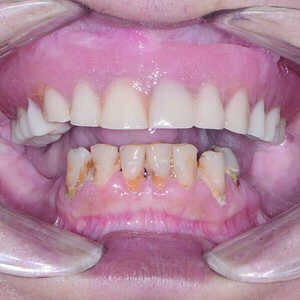

Une patiente dans la cinquantaine a consulté mon cabinet pour le traitement de son maxillaire édenté et de ses dents mandibulaires extrêmement déchaussées et cariées (Figs. 1 et 2). La patiente était une grande fumeuse, n’avait consulté aucun dentiste depuis plusieurs années, et négligeait de prendre soin de ses dents restantes en raison de l’inconfort et de la douleur qu’elle ressentait.

Fig-1-Vue-préopératoire-avec-écarteur-de-lèvres-300x300-

Fig-2-Vue-préopératoire-avec-écarteur-de-lèvres-sans-prothèse-300x300-